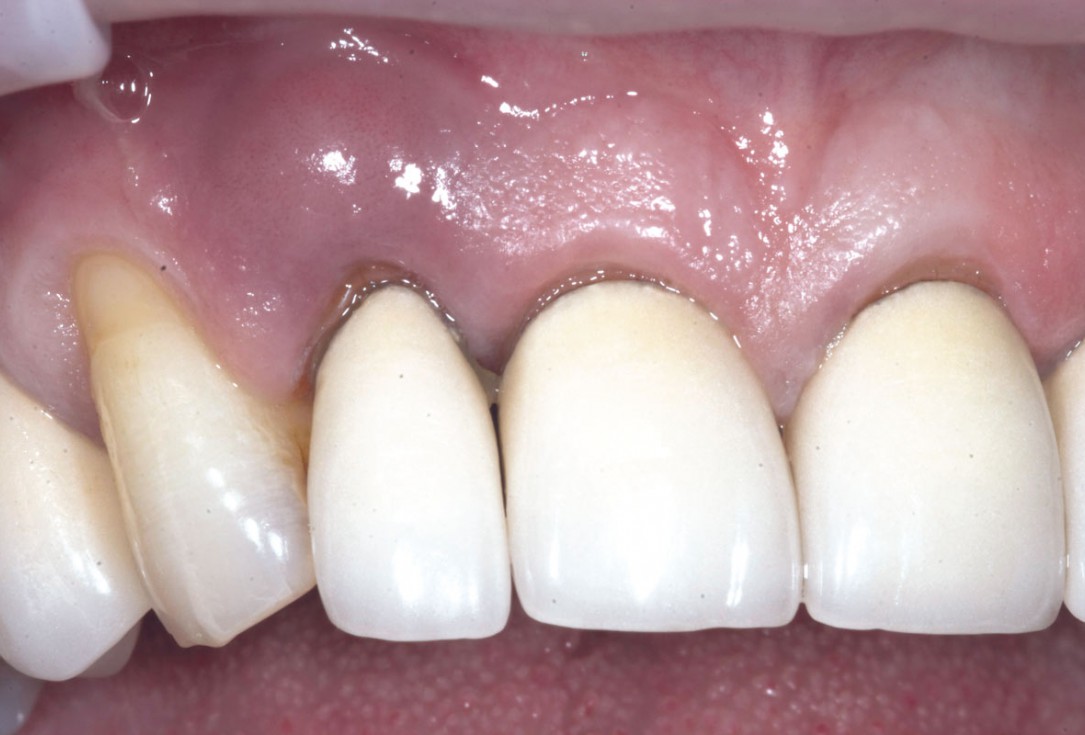

1/19 - Initial situation: Inflammated tooth #12Bone augementation with maxresorb® - Dr. R. Cutts

Initial situation: Inflammated tooth #12